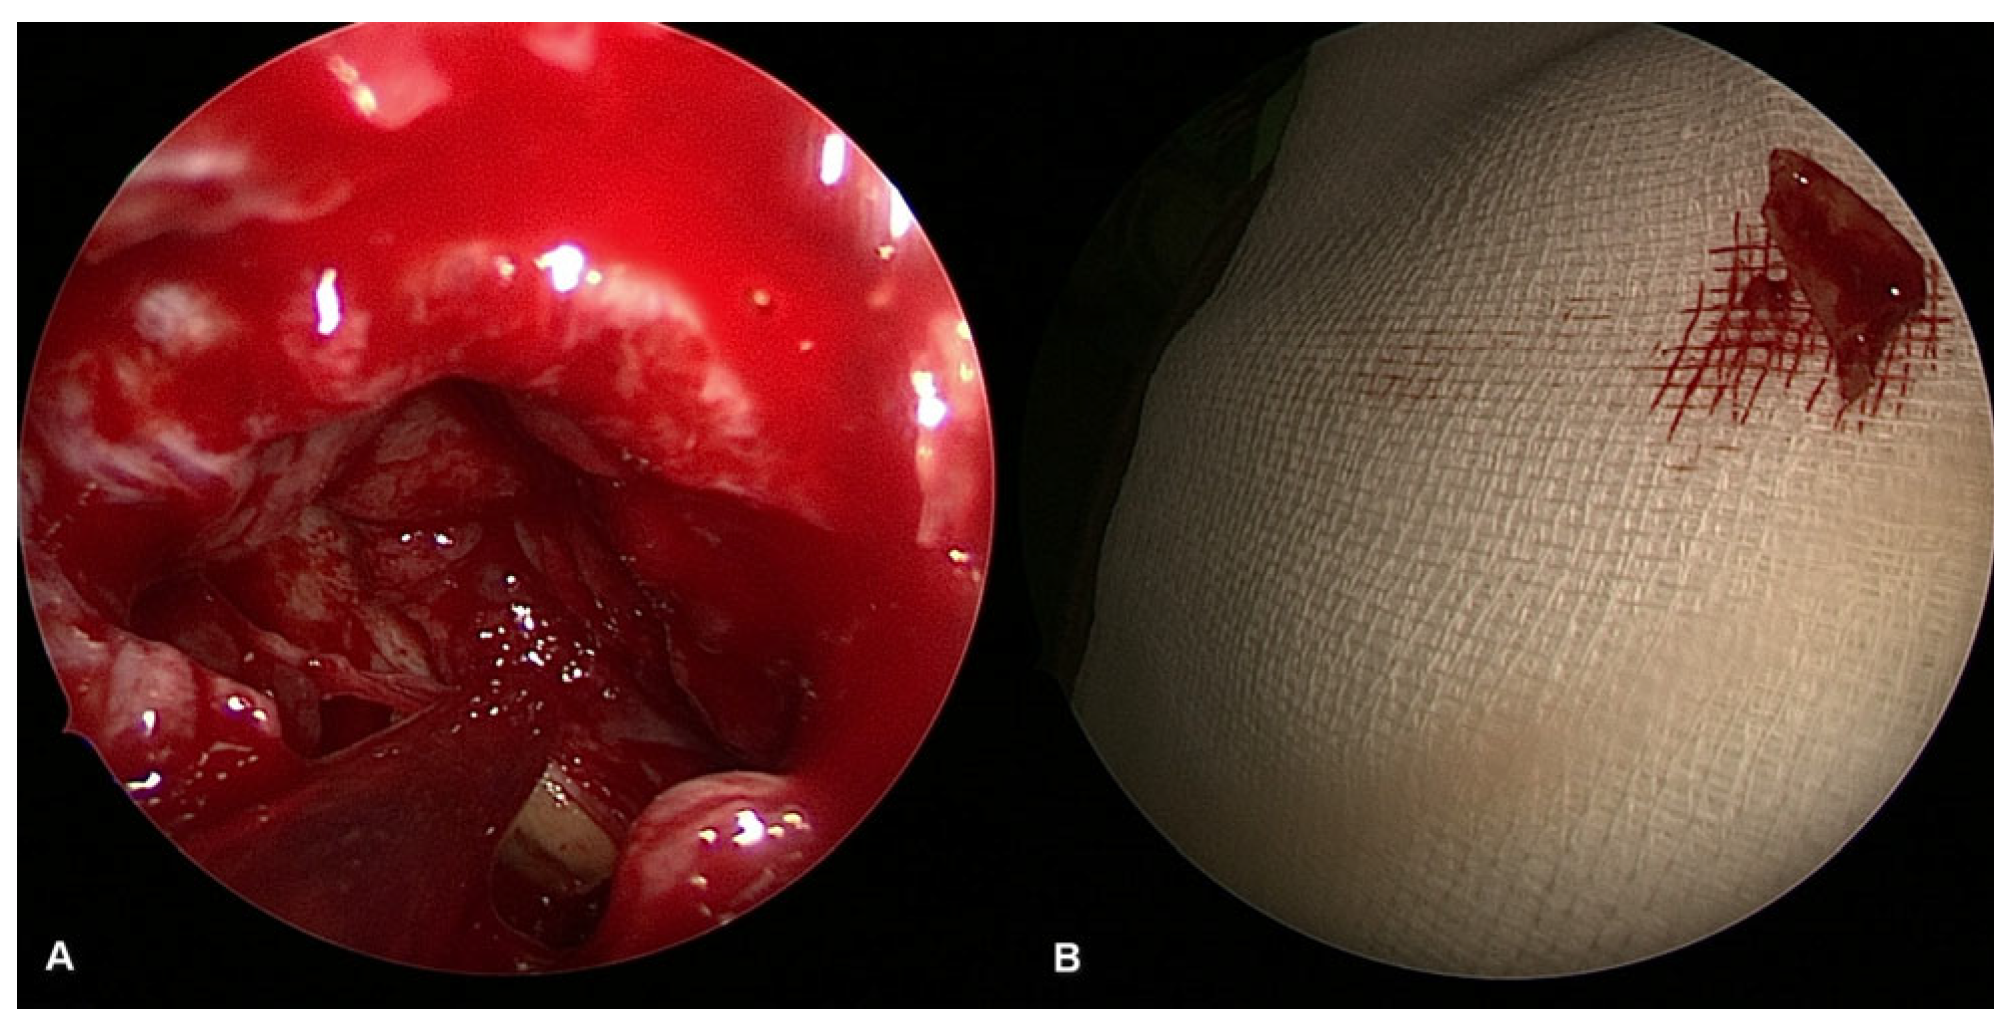

The first-line surgical treatment should be a combined FESS and oral surgery procedure such as tooth extraction, oro-antral fistula closure and foreign body removal (Figure 5), performed in a single session. The less commonly used procedures today are the Lothrop, Denker and Luc–Caldwell surgeries. Studies examining the effectiveness of simultaneous FESS and dentoalveolar surgery report better results compared to conservative therapy. According to most studies, the effectiveness of this treatment is reported to be between 95% and 100% after unsuccessful conservative therapy. FESS is a functional endoscopic sinus surgery based on a functional approach. The aim of this endoscopic procedure is to restore ventilation of the paranasal sinuses [6,12].

The therapy was always complex. In addition to FESS, fistula closure was indicated in 70 patients (63%), extraction in 64 patients (58%), foreign body removal in 4 patients (4%) (Figure 5), cystectomy in 7 patients (6%) and septoplasty in 10 patients (9%). Some patients required multiple dental interventions in addition to FESS surgery.

Figure 5. Surgical image of radix removal from the sinus cavity ((A): radix inside the maxillary sinus, (B): removed radix).